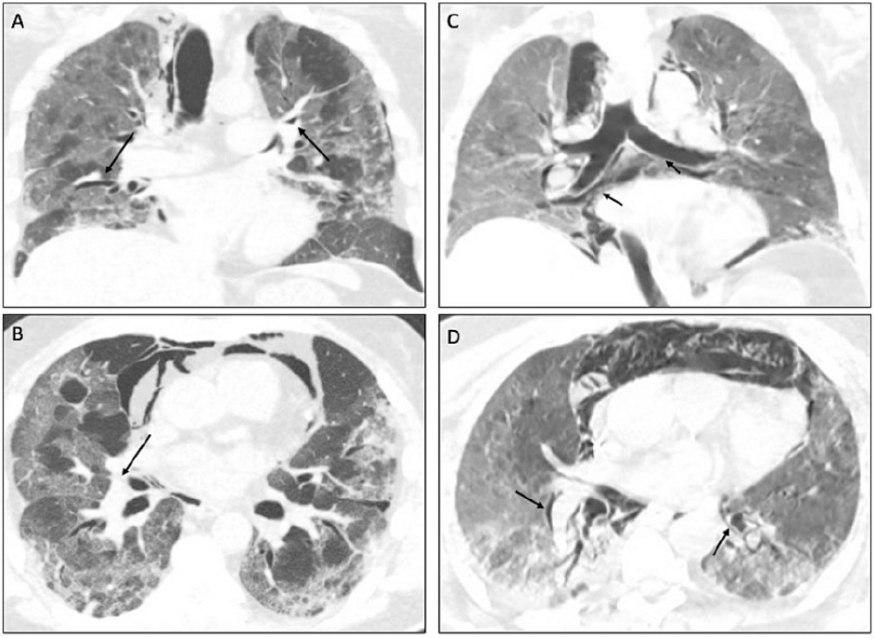

第1~10天,HFNC+清醒俯卧位。第2天,HFNC 50 L/min,FiO2 0.5,PFR 155 mmHg,RR 22~25 bpm。第8天,HFNC 50 L/min,FiO2 0.8,PFR 95 mmHg,RR 25~30 bpm。第10天,ET+IMV(因呼吸窘迫,PFR<100 mmHg)。

图片

第11天,气管切开+IMV。第13天,出现明显纵隔气肿。PCV:PC 12 cmH2O,PEEP 10 cmH2O,FiO2 0.55,PFR 154 mmHg,VT 7~9 ml/kg,RR 25~28 bpm,MV 12~14。顺应性(C)18 ml/cmH2O。第21天,家属放弃治疗。